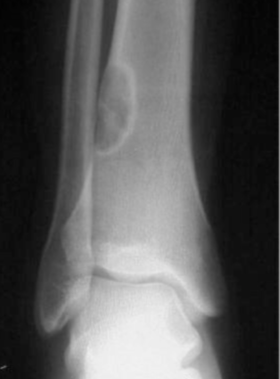

Ewing sarcoma